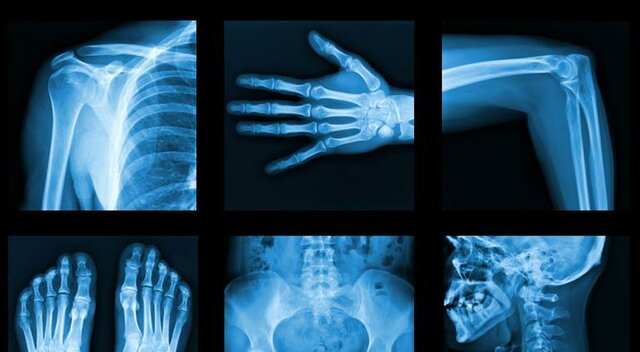

• Rayos X

Rayos X

Un procedimiento médico tan común como los rayos X fue descubierto por accidente. Su inventor fue Wilhelm Conrad Röntge, quien en 1895 descubrió que su tubo de rayos catódicos podría producir algunas imágenes inusuales.